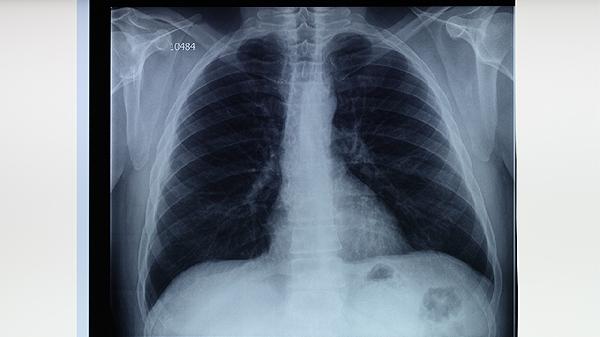

肺结核体检一般能查出来,主要通过胸部X线检查、痰涂片检查、结核菌素试验等方法进行筛查。肺结核是由结核分枝杆菌感染引起的慢性传染病,建议出现咳嗽、咳痰、发热等症状时及时就医检查。

肺结核体检中,胸部X线检查是最常用的筛查手段,能够发现肺部异常阴影,提示可能存在结核病灶。痰涂片检查通过显微镜观察痰液中是否存在抗酸杆菌,是确诊肺结核的重要依据。结核菌素试验通过皮内注射结核菌素,观察皮肤反应判断是否感染结核分枝杆菌。血液检查如γ-干扰素释放试验也有助于诊断。对于疑似病例,医生可能会建议进行痰培养检查,虽然耗时较长但准确性较高。